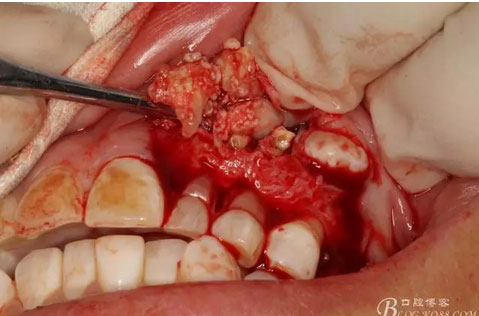

圖13.暴露出部分牙瘤

圖14.沿一側骨壁逐步剝離牙瘤組織。

圖15.剝離出來的多個成型小牙齒及致密鈣化物。

圖16.形態(tài)各異的小牙齒。

圖17.呼之欲出的巨大牙瘤組織。